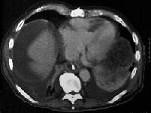

问题 87岁的甲状腺癌转移患者,傍晚行CT检查后死亡。CT图像如图所示,请选择正确的描述和结论 ( )

选项 A、考虑为右心室血栓 B、黏液瘤 C、该充盈缺损累及右心室流出道 D、未见异常发现 E、右心室见一不规则低密度充盈缺损

答案 ACE